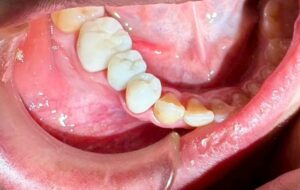

難しい 症例 です ので

上顎 は 完璧 なん です

下顎 に 少し 【スペース】が 生じました。

ご覧 の 通り

スペース が 狭すぎる の です。

完成した クラウン修復 は 【違和感】 ある くらい

小さな 【歯】に なって しまいます。

私は ブリッジ修復 を 選択しました。